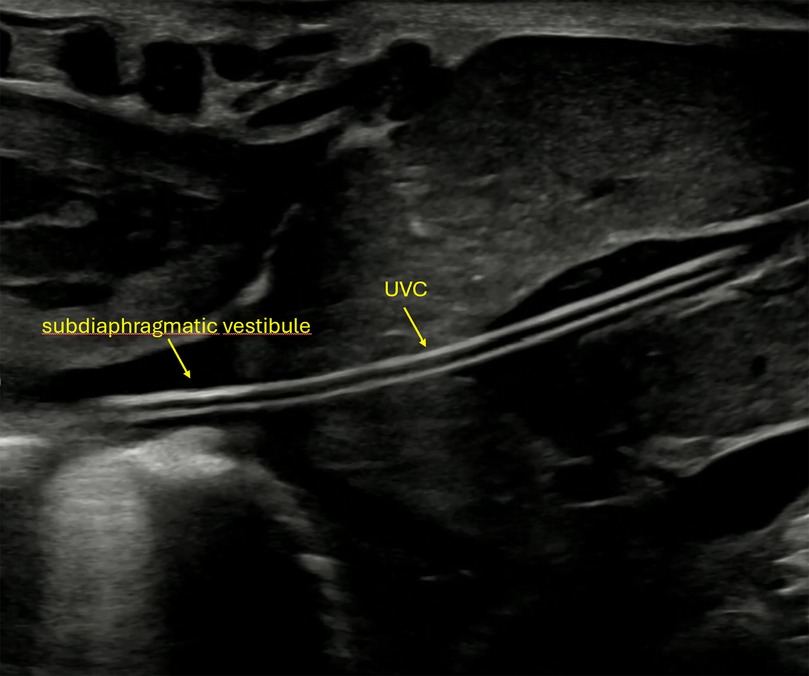

Figure 4

Ultrasound image showing the tip of the umbilical venous catheter (UVC) in the correct position in the subdiaphragmatic vestibule. Yellow arrows and labels identify each structure.

Figure 4. Ultrasound image showing the umbilical venous catheter (UVC) following successful advancement into the ductus venosus, confirming correct positioning.